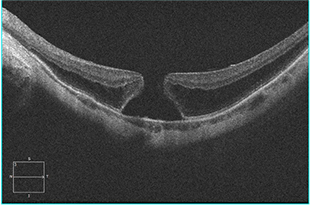

황반원공

황반원공이란?

망막 중심부에 위치하여 빛을 가장 선명하고 정확하게 받아들이는 황반 부분에 작은 구멍이 생기는 노인성 질환입니다.

증상

시력 저하가 나타나거나 시야가 흐려질 수 있으며 선이나 물체가 왜곡되어 보이는 변형시, 시야 중심에 암점이 생길 수 있습니다.

치료

망막 전문의 수술 (유리체절제술)

Q2A황반원공이 진단되면 대부분 수술이 필요합니다.

유리체 절제술을 시행하게 되는데 눈 속의 유리체를 제거한 뒤, 내경계막이라는 망막의 가장 안쪽 층을 제거한 후 가스를 주입합니다. 가스 주입은 황반원공이 좀 더 잘 회복될 수 있게하는 효과가 있습니다. 가스를 넣고 수술을 마친 후에는 엎드린 자세를 유지하는 것이 중요합니다. 엎드린 자세를 제대로 하지 않는 경우 시력이 덜 회복될 수 있습니다.